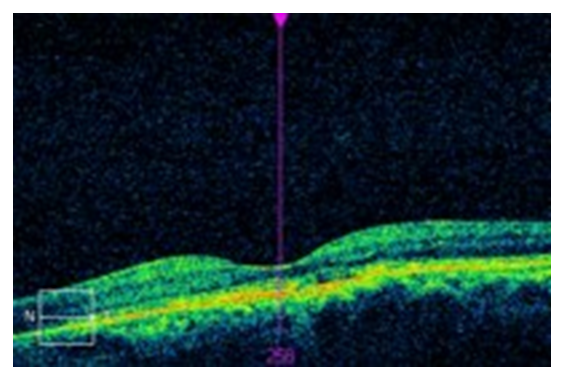

Dilated examination was performed with a 90D lens and binocular indirect ophthalmoscopy. The lens and vitreous was clear and intact in each eye. The peripheral and mid-peripheral retina in each eye was flat and intact, with no breaks or detachments 360. Optic discs were healthy and perfused with distinct margins in both eyes. The cup-to-disc ratios in the right and left eyes were recorded as 0.25/0.25 with no apparent nerve fiber layer dropout. Blood vessels in both eyes followed a normal course and caliber. The macula in the right eye was flat and intact with the presence of a foveal reflex. The macula of the left eye was mildly elevated, with no foveal reflexpresent. Due to the changes in macular appearance in the left eye, an OCT was performed revealing central serous chorioretinopathy.

(Figure 1 and 2)

Figure 2:OCT OS revealing serous macular detachment.

The use of OCT in the diagnosis and management of CSCR is beneficial in that it is a more readily available and less invasive modality than FA or angiography. In subtle cases where visionis mildly affected and the presence of subretinal fluid can be inconspicuous, the OCT will clearly reflect pathological changes[16]. Diagnostic characteristics on OCT include neurosensory retinal detachment, PED, fibrinous exudates, and cystic retinal changes[1]. More importantly, the OCT has been able to measure the thickness of the choroid, which is the main structure implicated in the CSCR, exhibiting a greater thickness in affected eyes[10]. PEDs are more readily observed using OCT than in more invasive techniques utilizing angiography[16]. More recent studies evaluated the appearance of specific retinal layers in CSCR, demonstrating that the photoreceptor (PR) outer segments are often thickening during the course of the disease, and display a granular appearance on imaging. The granular appearance is likely secondary to the accumulation of the discs that are shed[1]. Thickness of the outer nuclear layer was shown to correlate with visual acuity, as well as the reduced distance from the internal limiting membrane to the external limiting membrane[10].

The OCT is also helpful in monitoring the course of CSCR. In cases as presented here, the OCT was essential in the diagnosis and resolution of condition, as the patient was only mildly symptomatic and visual acuity generally unaffected. In cases where CSCR is treated, OCT is helpful in determining the effect of the treatment. Due to its ability to measure choroidal thickness, a 20% reduction in thickness has been detected in successful photodynamic therapy (PDT)[10].